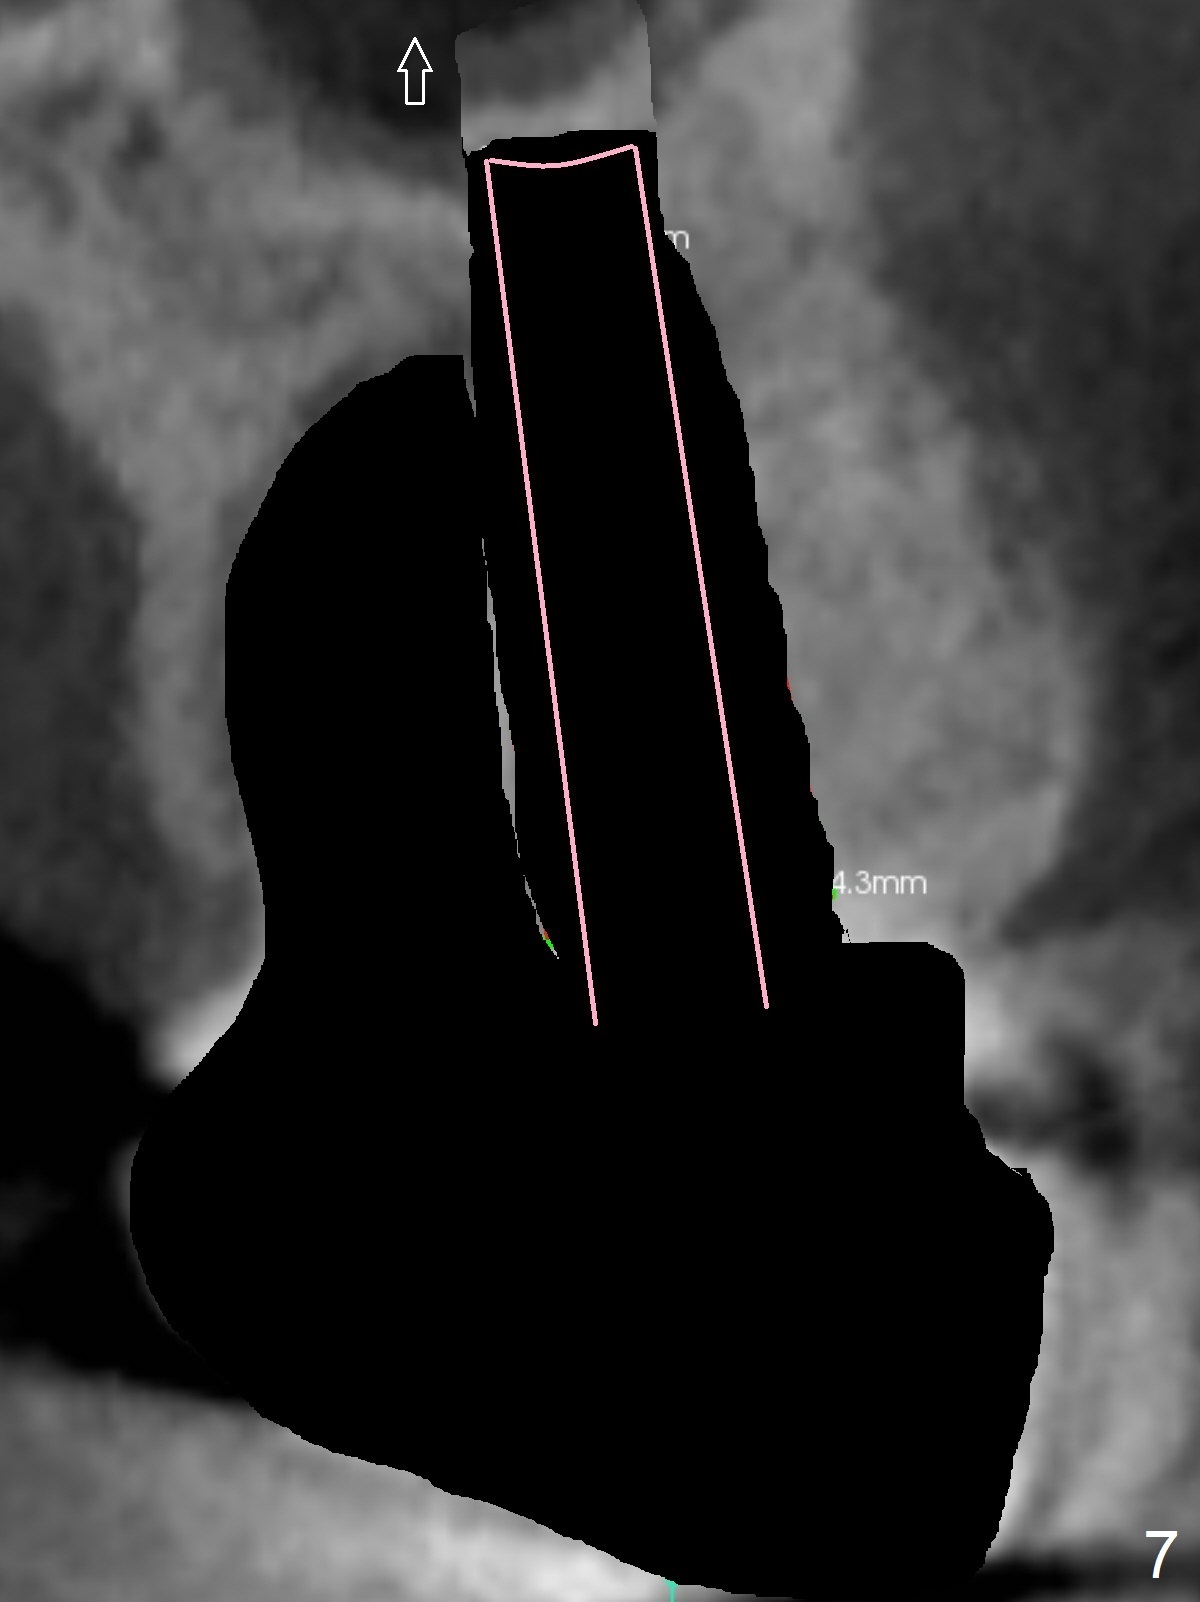

A 53-year-old man cannot chew on the left side with distal abscess in spite of RCT for #14 (* in Fig.1,2 (taken 11 ad 21 months postop, respectively)). After extraction (Fig.3 (CBCT coronal section) black area), start osteotomy with 2 mm drill (red outline) in the septum buccal to the palatal (P) socket). Following 2 mm drill removal (Fig.4), use 4.3 mm Magic Drill (red outline) for ~ 9 mm. When the osteotomy is being done, the osteotomy most likely shifts palatal (Fig.5 arrow) because of thin bone palatally. When the MD is removed (Fig.6), use Magic Sinus Lifter (Fig.7 pink) for sinus lift (arrow). The implant is to be 5x11 mm or larger. Because of the distal defect (Fig.1,2), start osteotomy mesially. Take Alginate impression before surgery for possible orthodontic treatment. Since bone density is high, use higher voltage and longer time for X-ray.